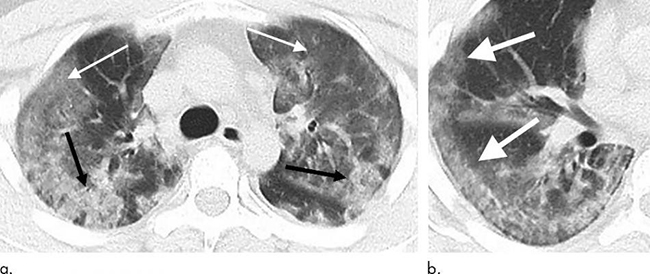

Ảnh chụp CT của bệnh nhân 15 tuổi, người từng đến Vũ Hán du lịch. Hình ảnh chụp CT được thực hiện sau 3 ngày kể từ khi có các triệu chứng nhiễm virus. Các nhà nghiên cứu đã tìm thấy những phát hiện mơ hồ trong phổi là dấu hiệu của coronavirus, không phải là dấu hiệu điển hình của các bệnh phổi khác. Mũi tên chỉ vào dấu hiệu của virus. (Ảnh: Dailymail)

Ảnh chụp bệnh nhân 65 tuổi, người từng đến Vũ Hán. Quét CT được thực hiện 11 ngày sau các triệu chứng xuất nhiễm Covid-19 xuất hiện. Các tổn thương mờ có hình dạng tròn xuất hiện nhiều trên phổi. (Ảnh: Dailymail)